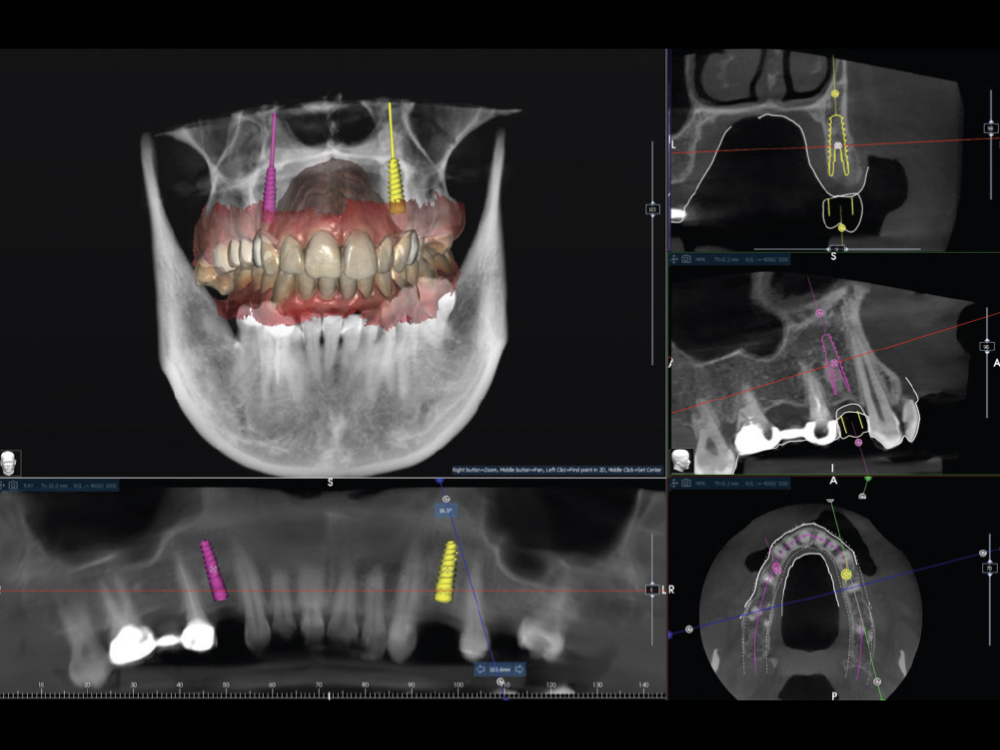

Comprehensive records were obtained, including a CBCT scan and a full-arch intraoral scan

Figure 2: Comprehensive records were obtained, including a CBCT scan and a full-arch intraoral scan. The data was transmitted to Glidewell’s Digital Treatment Planning (DTP) department, where the restorative and surgical plans were developed concurrently. The implants were virtually positioned to achieve ideal emergence profiles, screw-retained trajectories, and prosthetically driven alignment within the available bone.